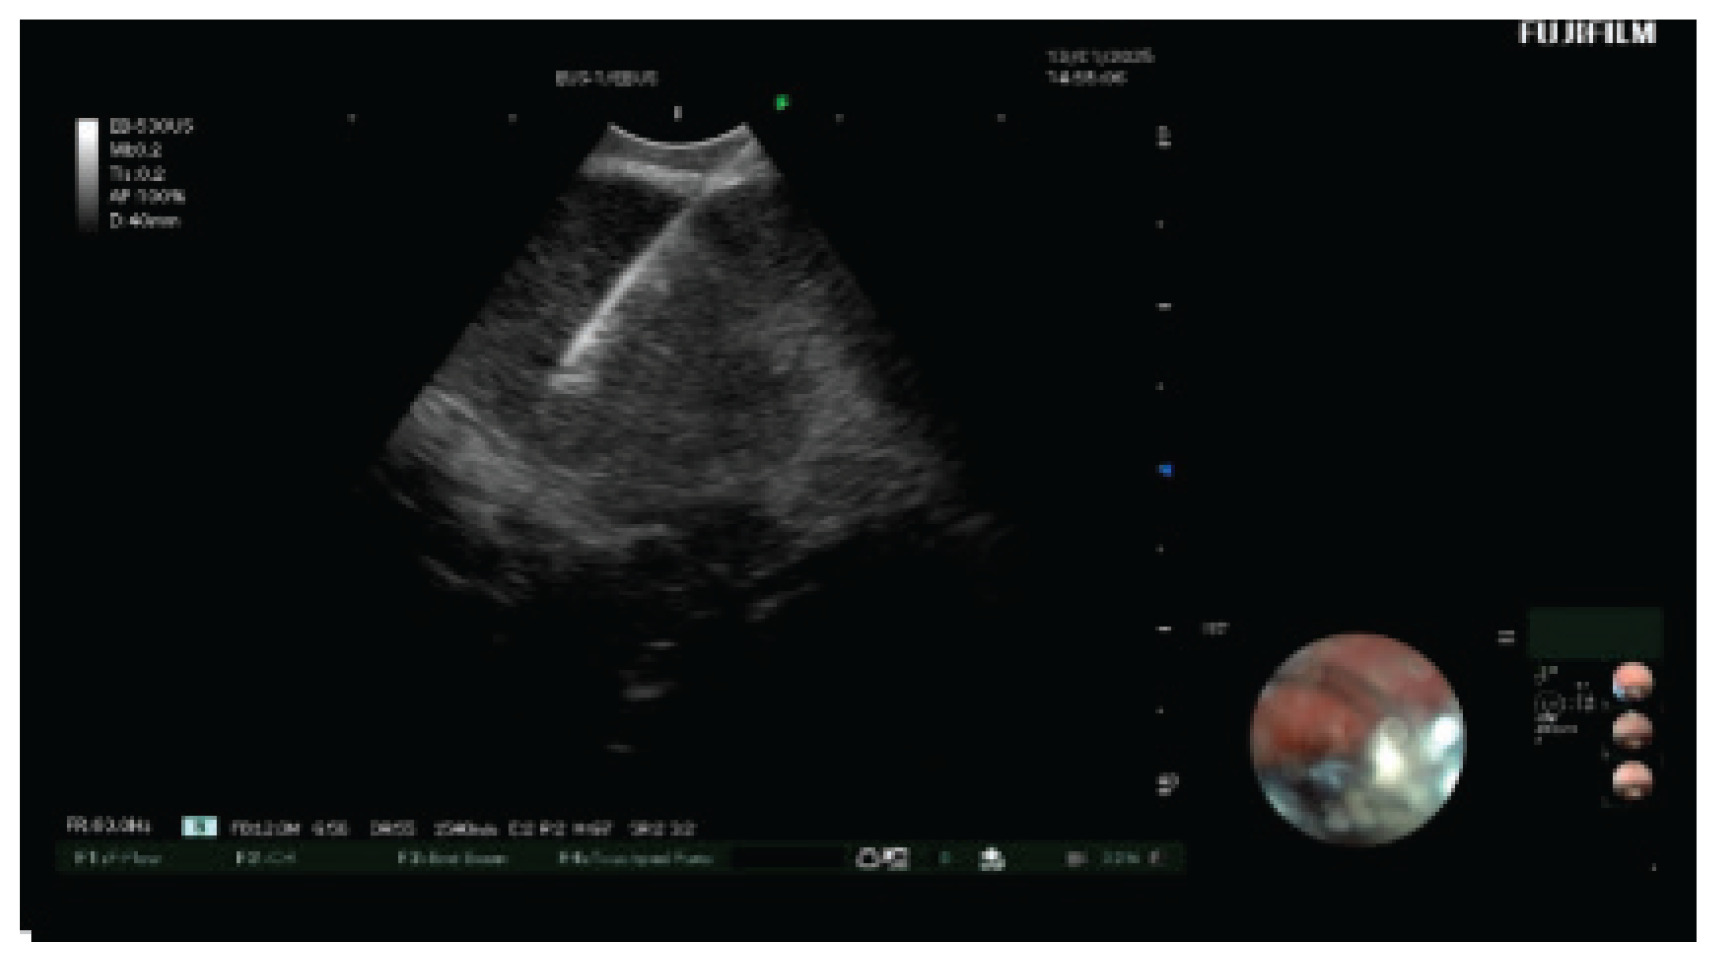

EBUS-TBNA was used to sample lymph node stations 4R, 7R, and 11R (Figure 3), and bronchoalveolar lavage (BAL) was performed in the right middle lobe. Histopathological analysis showed non-caseating granulomas with epithelioid histiocytes and surrounding lymphocytes (Figure 4), consistent with non-necrotic granulomatous inflammation. Rigorous laboratory and cytological examination of BAL suggested no other potential diagnosis.

Figure 4

Histopathology image of non-caseating granulomatous inflammation in the mediastinal lymph node: A) Four granulomas are seen with no necrosis in the center; B) Enlarged epithelial cells are in the center of the granuloma, surrounded by lymphocytes